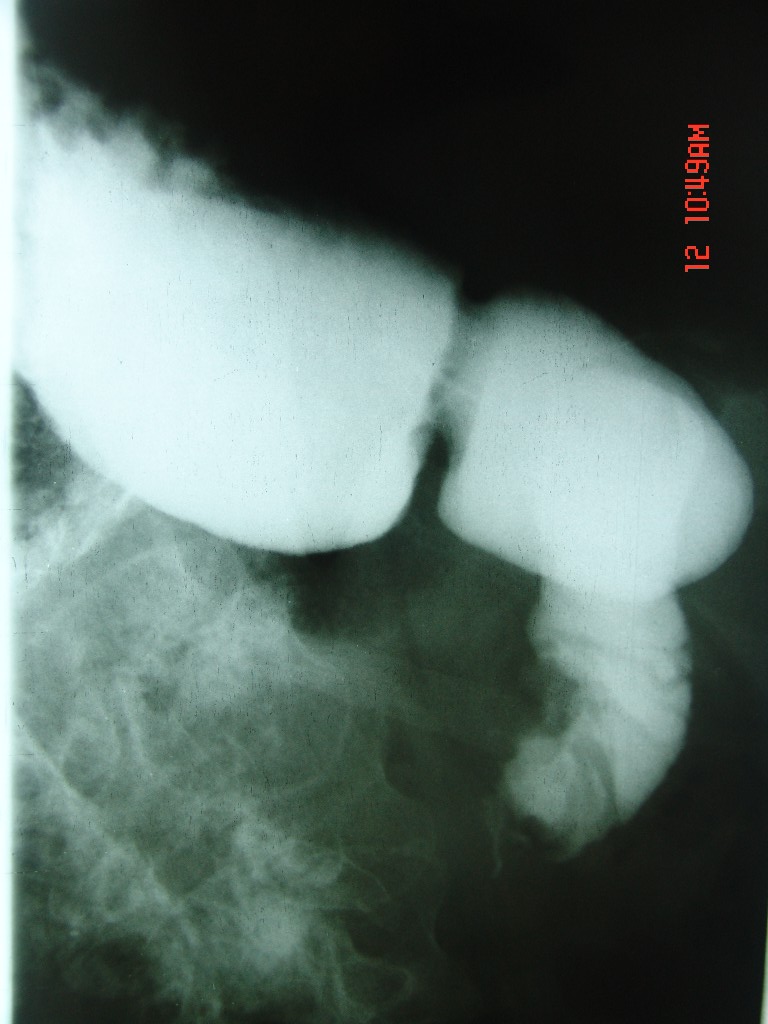

胃体部粘膜不规则增厚,胃肠造影也显示充盈缺损-胃溃疡?胃癌?

上消化道造影见十二指肠结节状充盈缺损,ct增强十二指肠壁局限性增厚并强化,考虑十二指肠壶腹癌?